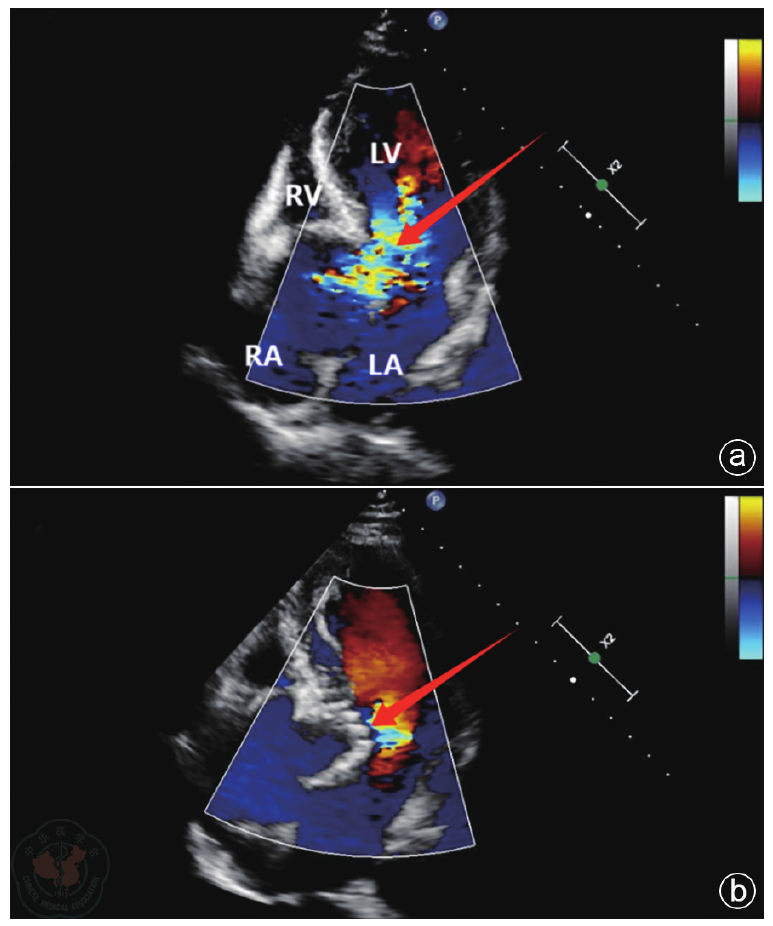

Methods The diagnosis and treatment data of one patient with severe AI admitted to the Air Force Medical Center on October 29, 2025, were retrospectively analyzed. Preoperative echocardiography was used to accurately assess valve structure (including number, morphology, echogenicity, etc.), the cause of regurgitation (including valve calcification, prolapse, perforation, annular dilatation, etc.) and its severity (including the ratio of regurgitant jet width to left ventricular outflow tract width, regurgitant area and length, Doppler spectra, etc.). Key aortic root dimensions were measured (including valve orifice area, aortic annulus, sinus of Valsalva, sinotubular junction, and ascending aortic diameters) to provide a basis for selecting the appropriate J-VALVE TF prosthesis size. Intraoperative ultrasound served as a real-time " navigation" system, guiding the entire process of device delivery and deployment, and providing immediate assessment of prosthesis position, function, and the presence of paravalvular leakage. Postoperative ultrasound served as the primary follow-up tool to evaluate prosthetic valve function and cardiac chamber reverse remodeling.

Results The patient experienced chest tightness and shortness of breath one year prior while lying flat at night. Symptoms could be induced by exertion or insomnia, lasted approximately one minute, and could be relieved by taking a deep breath. Echocardiography indicated: aortic developmental anomaly, aortic valve insufficiency with massive regurgitation, dilatation of the aortic sinus, and widening of the ascending aorta. Based on clinical presentation and echocardiographic findings, the patient underwent TAVR using the J-VALVE TF valve system. Intraoperative ultrasound provided real-time guidance during the delivery and deployment of the J-VALVE TF valve, monitoring the deployment process and the relative position of the delivery system. It was used to assess potential impacts on the mitral valve and coronary ostia before deployment and to evaluate prosthetic valve function after deployment. Postoperative assessment focused on the presence of paravalvular leakage, cardiac function, and the recovery of cardiac chamber geometry.